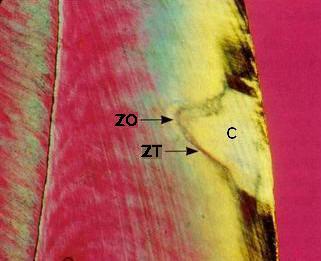

La figuras (izquierda)

muestran una sección longitudinal por desgaste, examinada

al microscopio con luz transmitida:

-

Zona superficial

(ZS): Es poco afectada porque recibe

minerales del cuerpo de la lesión

(1-2%

de porosidad)

-

Cuerpo de

la lesión (C):

Es el

área de mayor

desmineralización

(25-50%

de porosidad)

-

Zona

oscura

(ZD):

Desmineralización

(5-10%

de porosidad)

-

Zona

translúcida

(ZT):

No siempre está presente,

se encuentra en el avance

frontal

de la lesión,

ligeramente

más poroso

que el esmalte

sano,

la pérdida

de minerales

es del 1%